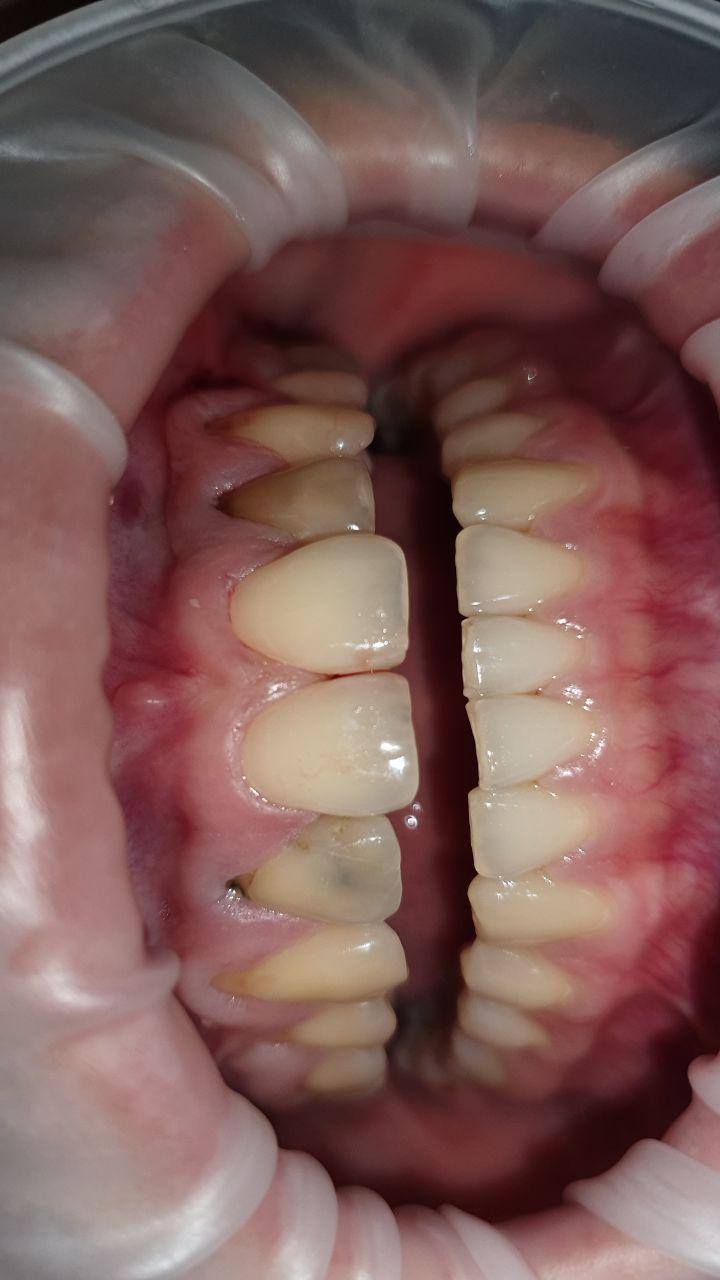

Пародонтит- воспаление десен с нарушением целостности зубодесневого соединения, сопровождающееся образованием патологического кармана и убылью костной ткани. Поражает практически все возрастные группы населения, в том числе молодых людей и даже детей. Именно они приводят чаще всего к потере зубов вследствие выраженного деструктивного процесса, обусловливая стойкие нарушения функции зубочелюстной системы.

- Подвижность зубов

- Обнажение корней зубов

Кюретаж пародонтальных карманов- процедура по удалению поддесневых зубных отложений (т.е. микробного налета) с последующим сглаживанием поверхности корня, которая способствует восстановлению прикрепления десны к корню зуба. Чаще, процедура проводится под анестезией. Для поддержания здоровья десен процедуру необходимо проводить раз в 6 месяцев.